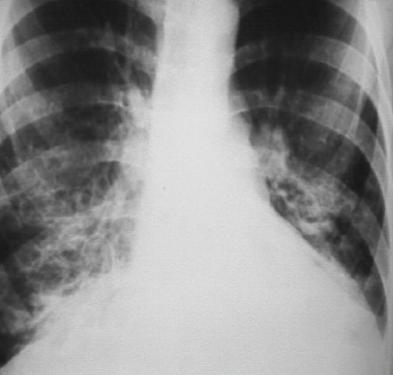

1、X线:病情较轻时仅表现为肺纹理增粗,病情加重时双肺可见环状透光阴影,呈卷发状或蜂窝状,常伴肺段或肺叶不张及炎症浸润阴影。

典型支气管扩张,肺野内不规则的卷发状、蜂窝状阴影。